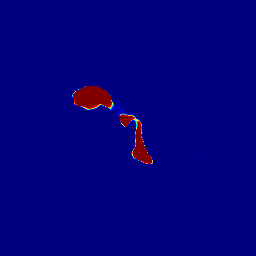

Finally, Fig. 9 displays examples of output probability maps from all of the comparative methods, i.e., HNN [12], UNet [16], PNet-MSA and “PNet-MSA+BiRNN”, where the latter one delivers the sharpest and clearest output on both CT and MRI datasets. More specifically, PNet-MSA presents results that are detailed and recover the major part of the pancreas, where both HNN and UNet suffer from significant low segmentation recall. When observing the BiRNN outputs for CT and MRI, we find detailed pancreas parts in CT have been recovered via shape continuity learning and regularization, while in MRI, the BiRNN only outputs probability map with the same shape in PNet-MSA’s output, which is optimal when the inter-slice shape changes drastically in the MRI dataset. Thus, BiRNN would help to refine pancreas segmentation with a smoothed surface in the situation that slice thickness of the 3D scans is reasonably small, e.g., <2absent2<2mm.

Refer to caption

(a)

(b)

(c)

(d)

(e)

(f)

(g)

(h)

(i)

(j)

(k)

(l)

(m)

(n)

(o)

(p)

(q)

(r)

(s)

(t)

(u)

(v)

(w)

(x)

Figure 9: Examples of output probability map: columns from left to right are the input CT/MRI image, results from HNN [12], UNET [16], the proposed PNet-MSA sub-network, and the full CNN-RNN (“PNet-MSA+BiRNN”), and the ground truth. Our model delivers the most clear probability maps which preserve detailed pancreatic boundaries.